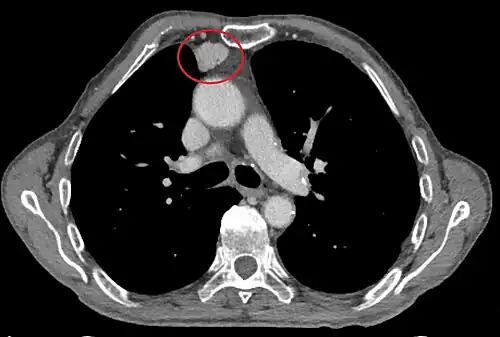

Scanner injecté, en fenêtre médiastinale, montrant un carcinome thymique envahissant les structures médiastinales :

1 : tumeur hétérogène, aux contours irréguliers, présentant des plages hémorragiques ;

2 : veine cave supérieure ;

3 : tronc artériel brachiocéphalique ;

4 : artères sous-clavière gauche et carotide commune gauche ;

5 : crosse de l'aorte ;